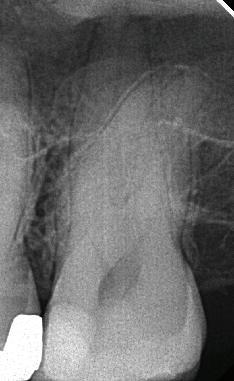

EdgePRO® provides outstanding Cleaning, Debridement and Disinfection by removing infected tissue, biofilm and smear layer killing up to 99% of bacteria commonly found in the root canals. (1,2,3,4) This should give you the confidence you need to treat even the most complex anatomies.

Provides outstanding Cleaning, Debridement and Disinfection by removing infected tissue, biofilm and smear layer killing up to 99% of bacteria commonly found in the root canals. (1,2,3,4) This should give you the confidence you need to treat even the most complex anatomies.